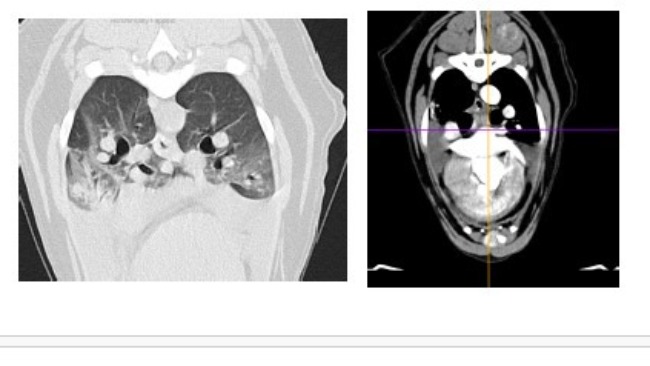

Wyniki badania krwi są stabilne. Płyny w jamie opłucnej są w śladowej ilości. Guz tym razem nie był widoczny na USG. Natomiast lekarz onkolog odkrył dwa guzy na śledzionie, które będą obserwowane i być może będą wymagały biopsji.

Dodatkowo ustaliliśmy, że guza w klatce piersiowej na razie nie ruszamy, ponieważ z płynów w jamie opłucnej zostały tylko śladowe ilości, a sam guz wygląda na zmniejszonego.

Chłoniak jest w częściowej remisji. Pozostaje płyn w jamie opłucnej oraz guz w śródpiersiu, który będzie diagnozowany. Kontynuacja leczenia za dwa tygodnie.